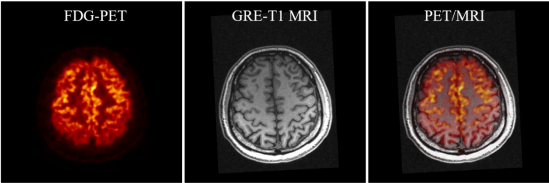

SIAT bPET和聯(lián)影uMR790 3T磁共振成像系統(tǒng)上同時獲得的人腦PET/MRI圖像